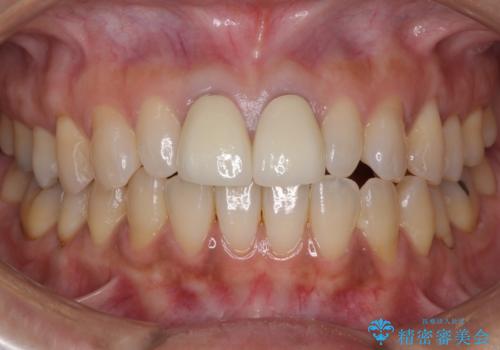

セラミック治療と根管治療を行いました。

金属を使用したメタルボンドクラウンが入っていたため、いつかオールセラミックにしたいときに根管治療も行ったほうが良いとご提案し、今回行いました。

色について

歯と歯肉の境目の色は、歯自体が黒くなっている場合、完全にカバーすることは難しいです。